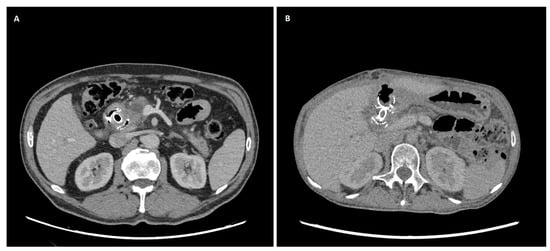

Background: After a failed endoscopic retrograde cholangiopancreatography (ERCP) for malignant biliary obstruction (MBO), second-line drainage is performed with endoscopic ultrasound-guided biliary drainage (EUS-BD) or percutaneous transhepatic biliary drainage (PTBD). We compared their effectiveness, safety, and short-term survival. Methods: We conducted a single-center retrospective cohort of 101 adults with MBO after they had experienced a failed ERCP (EUS-BD n = 37; PTBD n = 64). Allocation was non-randomized and driven by operational availability. Baseline laboratory tests (complete blood count, platelets, and C-reactive protein) and derived indices (neutrophil-to-lymphocyte ratio [NLR], platelet-to-lymphocyte ratio [PLR], lymphocyte-to-monocyte ratio [LMR], systemic immune-inflammation index [SII], systemic inflammation response index [SIRI], neutrophil-to-platelet score [NPS], and lymphocyte-to-CRP ratio [LCR]) were compared. Outcomes that were a technical success include: an early biochemical response (bilirubin reduction), complications (Clavien–Dindo), length of stay (LOS), and overall survival (OS). Between-group comparisons used the two-sided Mann–Whitney U test (continuous) and Fisher’s exact (binary) test. Survival was assessed by the Kaplan–Meier estimator using log-rank testing. To address later adoption of EUS-BD, we also estimated a restricted mean survival time of 180 days (RMST_0–180) with 95% confidence intervals (CIs). Results: Baseline inflammatory markers and composite indices were similar; baseline total bilirubin was higher in PTBD. The technical success was 100% in both groups. Early biochemical response was 86.5% after EUS-BD vs. 78.1% after PTBD (p = 0.43). Any complication occurred in 29.7% vs. 12.5% (p = 0.04); major complications (Clavien–Dindo ≥ III) occurred in 10.8% vs. 0% (p = 0.02), respectively; and the LOS did not differ (p = 0.21). OS favored EUS-BD (median 143 vs. 54 days and log-rank p = 0.012). RMST_0–180 was 111.1 days for EUS-BD vs. 71.4 days for PTBD (difference + 39.6 days; 95% CI 11.3–65.9). Conclusions: After a failed ERCP for MBO, EUS-BD and PTBD achieved universal technical success and similar early biochemical responses, but EUS-BD was associated with higher complication rates and a significantly longer six-month survival. These findings support the individualized selection balancing procedural risk with the anticipated survival benefit and highlight the need for prospective comparative studies. Full article

Show Figures

Figure 1